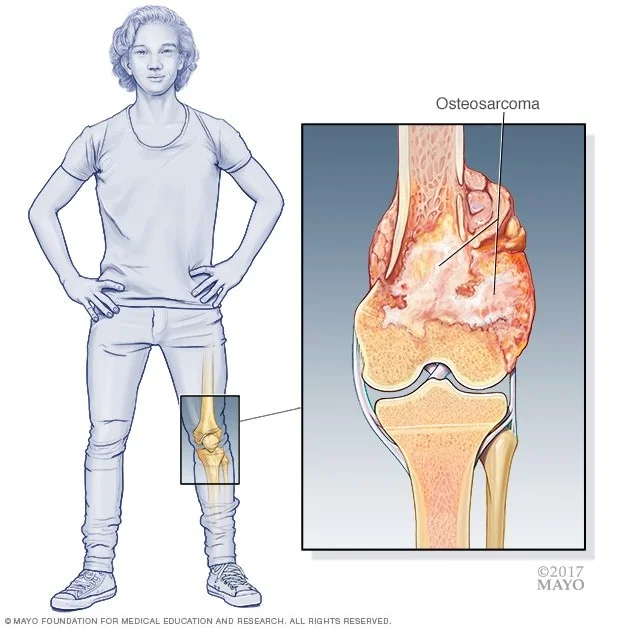

استئوسارکوم (که به آن سارکوم استخوانی نیز میگویند) شایع ترین نوع سرطان است که از استخوانها شروع میشود. سلولهای سرطانی در این تومورها شبیه اشکال اولیه سلولهای استخوانی هستند که به طور معمول به ساخت بافت استخوانی جدید کمک میکنند اما بافت استخوانی در استئوسارکوم به اندازه استخوانهای طبیعی قوی نیست.

در کودکان، نوجوانان و بزرگسالان جوان، استئوسارکوم معمولاً در مناطقی شروع میشود که استخوان به سرعت در حال رشد است، مانند نزدیک انتهای استخوانهای پا یا بازو:

- اکثر تومورها در استخوانهای اطراف زانو یا در قسمت تحتانی استخوان ران (دیستال فمور یا distal femur) یا قسمت فوقانی استخوان ساق پا (درشت نی پروگزیمال یا proximal tibia) ایجاد میشوند.

- استخوان بازو نزدیک به شانه (پروگزیمال هومروس یا proximal humerus) شایع ترین محل بعدی است.

با این حال، استئوسارکوم میتواند در هر استخوانی، از جمله استخوانهای لگن (hips)، شانه، و فک ایجاد شود. این امر به ویژه در افراد مسن صادق است.